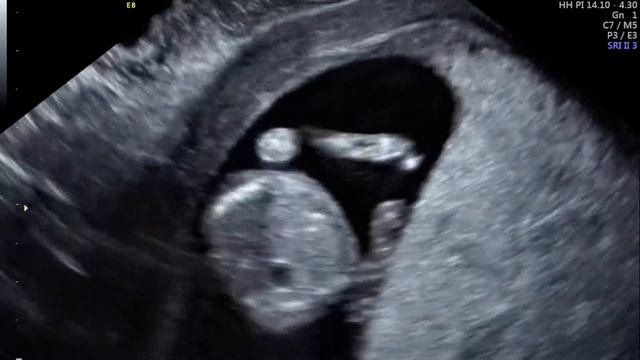

22 недели видео

22 недели видео 114 фото